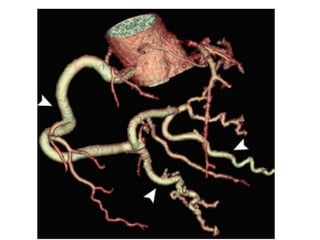

Coronary Aneurysms and Ectasia

Coronary Aneurysms andEctasia • Terminology and Classification • Etiology and pathogeneisis • Examples